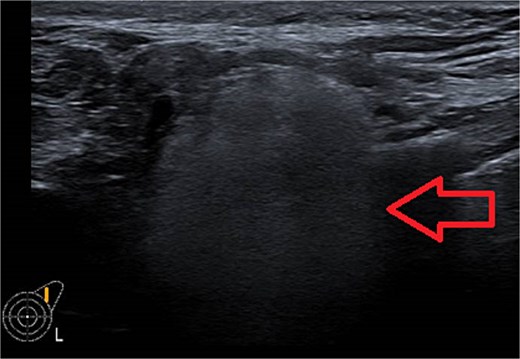

Ultrasound of left breast and axilla: Revealed rupture of the left implant with intracapsular and extracapsular leakage, along with echogenic peri-implant fluid. Enlarged axillary lymph nodes were visualized (Figs 1 and 2).

Ultrasound of the left breast showed rupture of the left breast implant with intracapsular and extracapsular leakage, surrounded by echogenic peri-implant fluid.